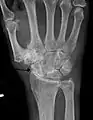

وعادة التغيرات الملاحظة في الأشعة السينية لا تتواءم مع الصورة السريرية كون معظم المرضى لا يشعرون بأي آلام بالمفاصل. الاختبارات الأخرى تشمل التصوير بالرنين المغناطيسي وأخذ بزل المفصل وتنظير المفصل.[51] في عام 1990 ، قامت الكلية الأمريكية لأمراض الروماتيزم، باستخدام بيانات من دراسة متعددة المراكز، بتطوير مجموعة من المعايير لتشخيص هشاشة العظام على أساس تضخم الأنسجة الصلبة وتورم بعض المفاصل.[52] تم العثور على هذه المعايير لتكون حساسة بنسبة 92٪ و 98٪ محددة لالتهاب المفاصل العظمي اليدوي مقابل الكيانات الأخرى مثل التهاب المفاصل الروماتويدي .[53]

هشاشة العظام الشديدة وهشاشة العظام في المفصل الرسغي